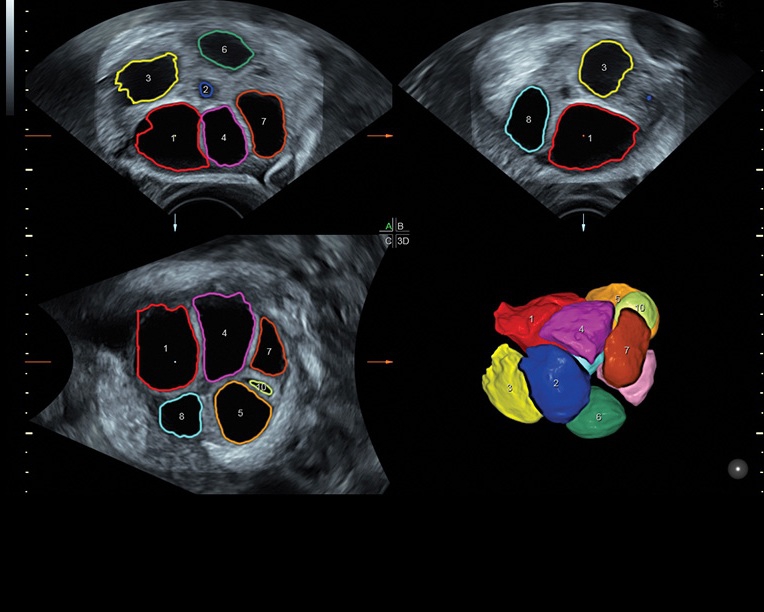

Система предназначена как для коммерческой, так и для государственной медицины, в клиниках с высокой загруженностью пациентами. Voluson S8 отлично справляется с большим объемом работы благодаря шаблонизированным отчетам и автоматизации обработки и постановки диагнозов с помощью функций SonoNT, SonoVCAD, SonoAVC и STIC. Это делает аппарат коммерчески выгодным и окупаемым в ближайшей перспективе.

• Сложные инструменты для оценки качества плода: Сканер оснащен инновационными инструментами, позволяющими проводить детальную оценку состояния плода, включая его сердечную деятельность, анатомию и кровоток.

• Технология SonoRenderlive: Эта технология облегчает получение 3D/4D изображений путем автоматического изменения положения плоскости визуализации в зависимости от движений плода. Она позволяет получить реалистичные и объемные изображения, что полезно для демонстрации плода будущим родителям и для дополнительного анализа.

• Программа для исследований сердца плода с возможностью цветовых допплеровских и ангиографических исследований на основе анализа пространственно-временной корреляции изображений (STIС)

• Программное обеспечение для исследования сердца плода в режиме 3D/4D (быстрый доступ к плоскостям сканирования) по рекомендациям ISUOG